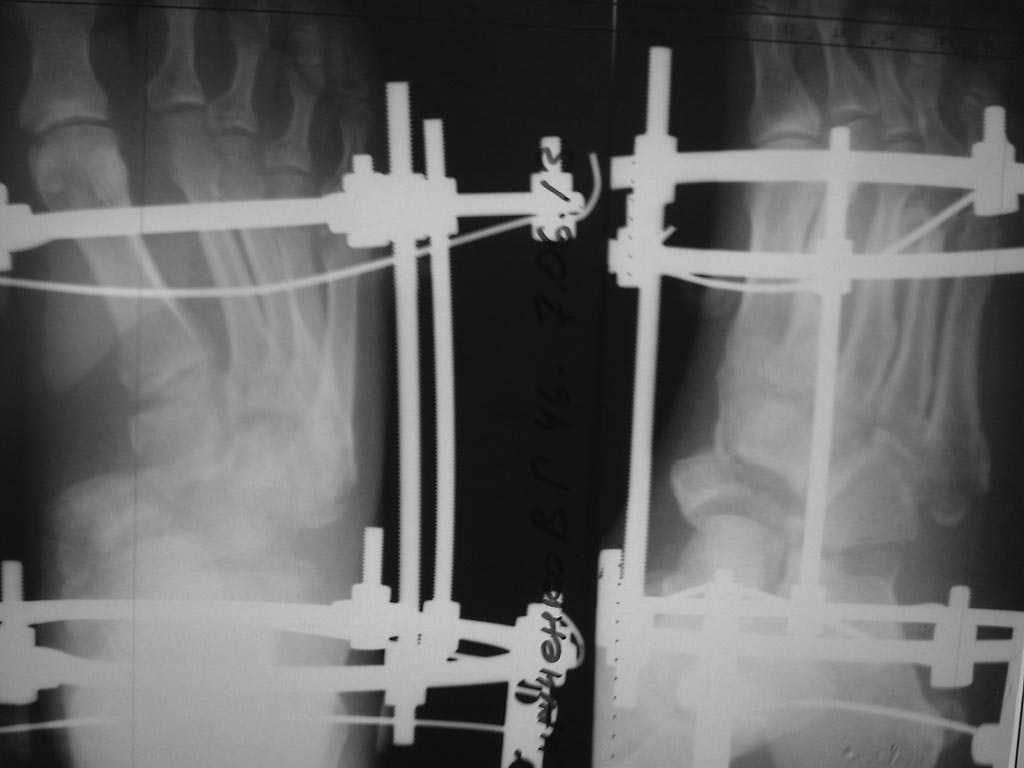

[Ortho] застарелый переломовывих в суставе Шопара

Обратился пациент 40 лет через 2,5 мес после травмы,

не курит, социален. Первым этапом наложили дистрактор, дозированная

дистракция, вторым этапом планировали репозицию ладьи с bridge plate

(шейка - клин). После выходных обнаружили такую картинку некрозов,

доступ планировался именно так. Считаю, что основная проблема в

ладье. Фрагмент ладьи абс неподвижен. Вопросы: стоит рисковать или нет?

будет ли менее рискованная операция позже по рубцу? Что еще следует

учесть (возможно недопонимаю анатомию повреждения)? Другие варианты?